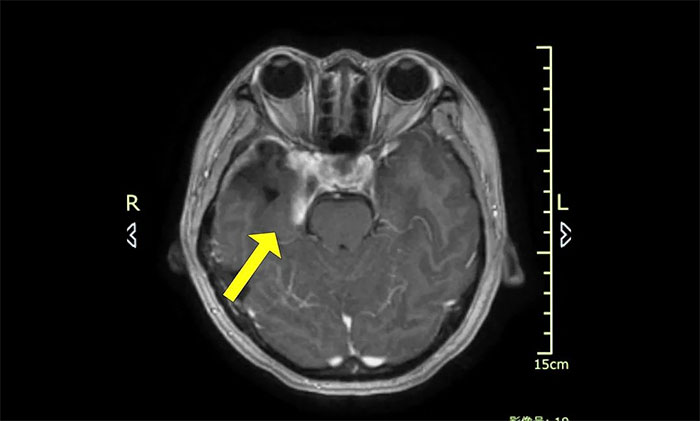

今年初医院收治了一位女性患者。该患者因突发视力模糊,头晕无法独立行走,在外院检查发现脑部右侧鞍旁肿块,手术病理诊断为海绵状血管瘤。

▲ 入院时MRI检查影像

肿瘤科(放疗)头部伽玛刀组陈琦主任完善检查并开展多学科评估讨论,其右侧鞍旁海绵状血管瘤与视神经等重要结构相邻,若不及时干预治疗,可因占位压迫进一步加重神经功能障碍,甚至导致失明。而该部位病灶的手术治疗难度高、风险大,术中可能对患者神经功能造成严重损害,应考虑采用创伤较小的伽玛刀治疗。